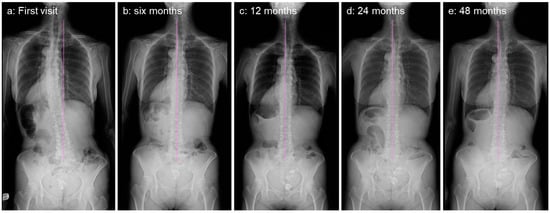

2.4. Image Examinations after Six Months of Daily Physical Exercise